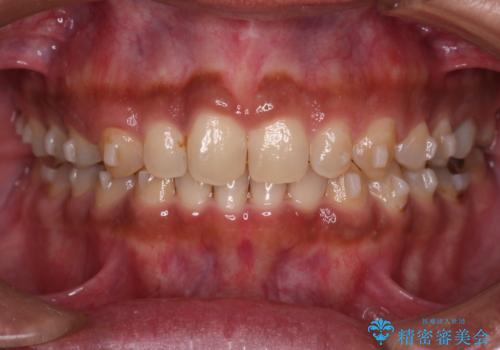

【モニター】インビザライン 前歯の捻れを治したい

- 30代男性

- 矯正装置

- インビザライン

- 治療期間

- 1年6ヶ月

- 上下の前歯のがたつきを主訴に来院されました。インビザラインで治療可能と判断致しましたので、IPR(歯と歯の間を削る処置)と歯列弓拡大をして

がたつきをとる治療計画を立てました。

マウスピースをしっかり使用していただいたことで、主訴である前歯のがたつきも改善され

リファイメントも1回のみで治療を終了することが出来ました。